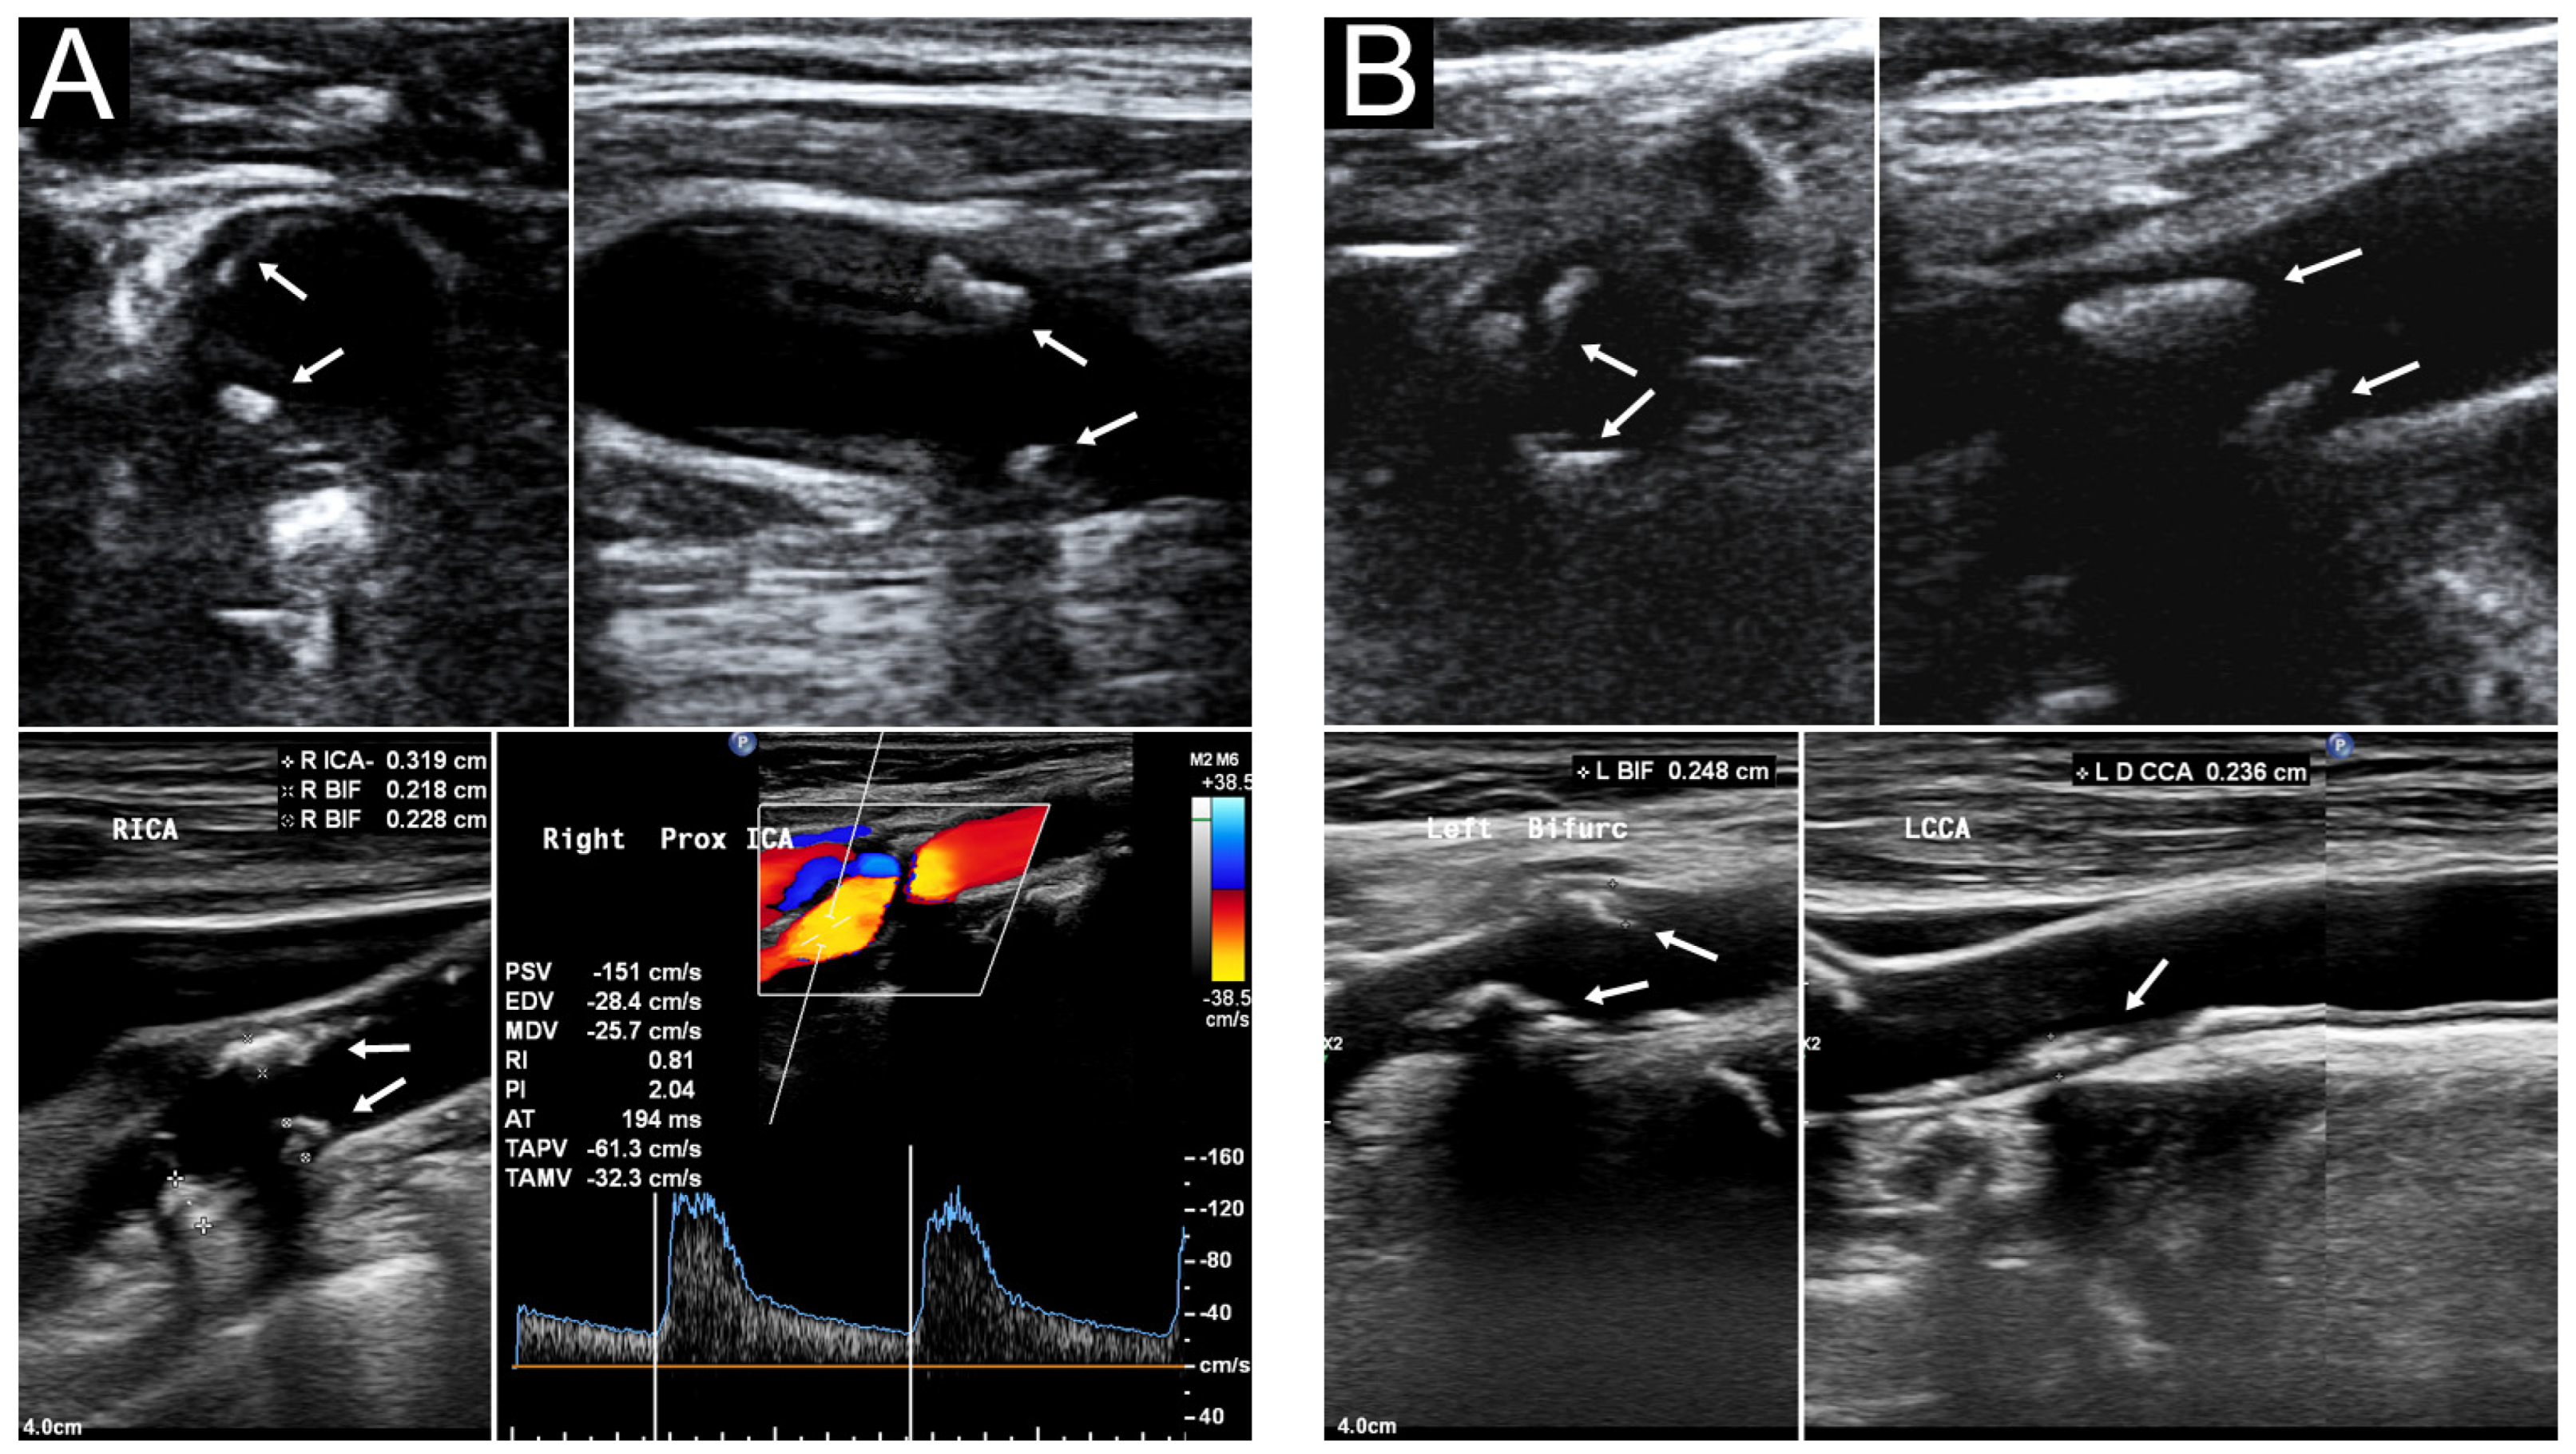

Figure 3 presents the sonographic findings of carotid plaques in a 91−year−old woman with a carotid risk score of 13. Table 4 summarizes the carotid sonography results of all 60 patients. We previously [13] reported that a median carotid risk score of 8 indicates a ≥63.7% risk of MHCA. The median outpatient and laboratory-derived sCPS was 2 (range: 0–6), and the median laboratory-derived hCPS was 5.0 (range: 0–19.5). No between-sex differences were noted in the sCPSs and hCPS. Thirty patients (50%) were found to have MHCA (hCPS > 5), which is consistent with our study revealing that a carotid risk score of ≥7 confers a 50% higher risk of MHCA [13]. No differences in risk factors were observed between patients with laboratory hCPSs ≤ 5 and those with laboratory hCPSs > 5 (Table 5). Patients with laboratory hCPSs > 5 had higher outpatient and laboratory sCPSs than those with laboratory hCPSs ≤ 5.

Figure 3.

Carotid ultrasound of a 91−year−old woman. Her outpatient sCPS, laboratory sCPS, and laboratory hCPS were 6, 6, and 19.5, respectively. (A) Segmental heteroechogenic plaques (arrows) were detected in the right carotid bifurcation (BIF) and internal carotid artery (ICA) through transverse (upper left) and longitudinal (upper right) POCUS performed in the outpatient department. Laboratory sonography revealed the same segmental plaques more clearly with various plaque thickness (lower left). Color duplex sonography indicated an elevated peak systolic velocity in the ICA (lower right). (B) Segmental plaques (arrows) were detected in the left carotid BIF and ICA through transverse (upper left) and longitudinal (upper right) approach POCUS. Laboratory sonography indicated more segmental plaques extending to the common carotid artery (lower right). BIF, right carotid bifurcation; hCPS, Handa’s carotid plaque score; ICA, internal carotid artery; POCUS, point-of-care ultrasound; sCPS, simplified carotid plaque score.